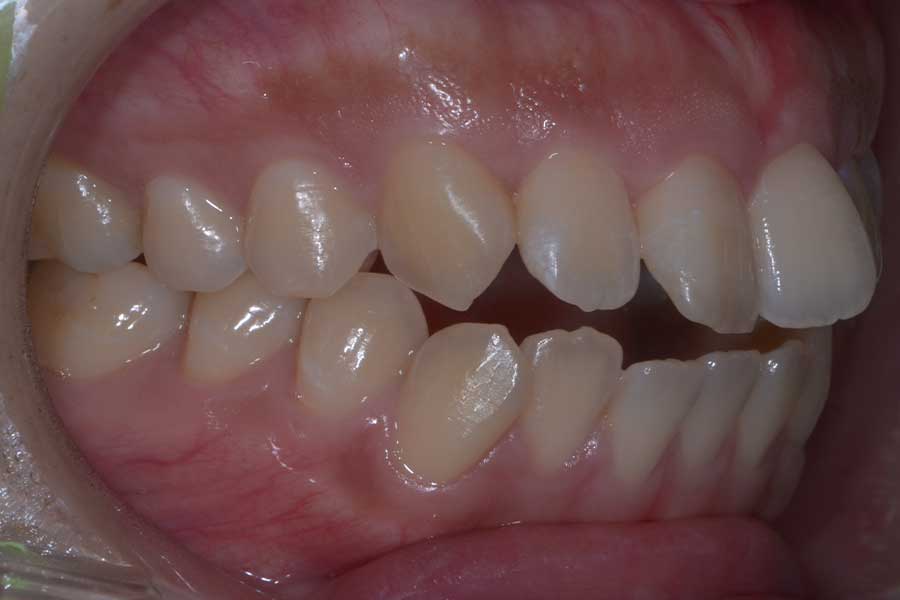

【20代女性】捻じれと段差と咬み合わせを治したい

• 治療前

主訴 捻じれと段差と咬み合わせを治したい

治療内容 上下顎ラビアル矯正(表側矯正)